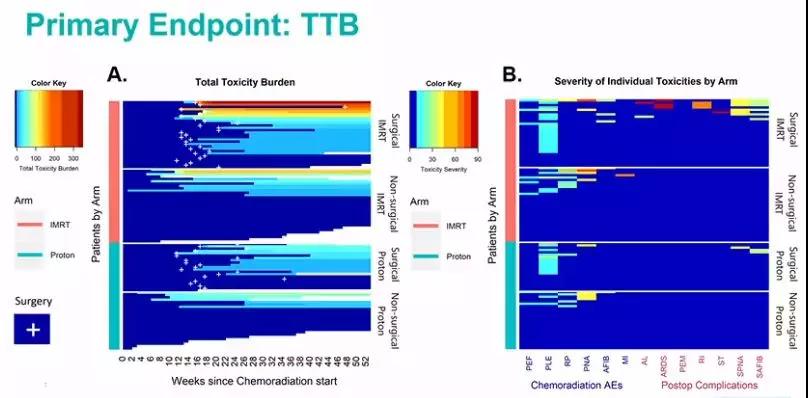

长期以来,人们都知道传统放疗使用的X射线(也称为光子)疗法会导致各种副作用,比如食管癌的放疗会造成不同程度的吞咽不适,脑瘤的放疗会导致精神不振等症状,但实际上接受...